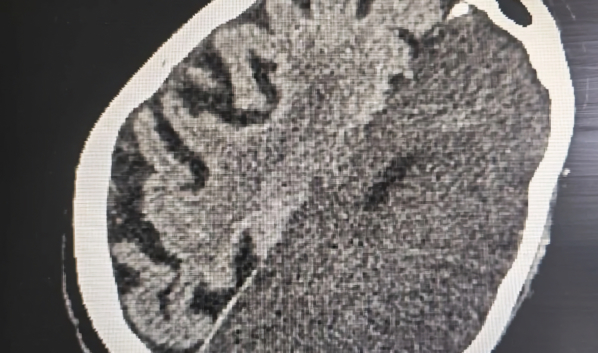

Компьютерная томография выявила обширный ишемический инсульт. При таком поражении происходит острое нарушение кровообращения и гибель клеток головного мозга. Медики подчёркивают, что подобные состояния относятся к наиболее опасным и сопровождаются высоким риском тяжёлых последствий.